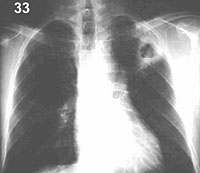

| ESQUEMA 33

Comentario placa 33 En el lóbulo superior izquierdo se observa una imagen similar a la anterior, de menor tamaño y rodeada de una condensación irregular del parénquima vecino. Plantea las mismas posibilidades etiológicas de la anterior, pero por su situación y aspecto obliga a descartar específicamente una caverna tuberculosa, mediante los exámenes correspondientes. Siga a la placa 34. |